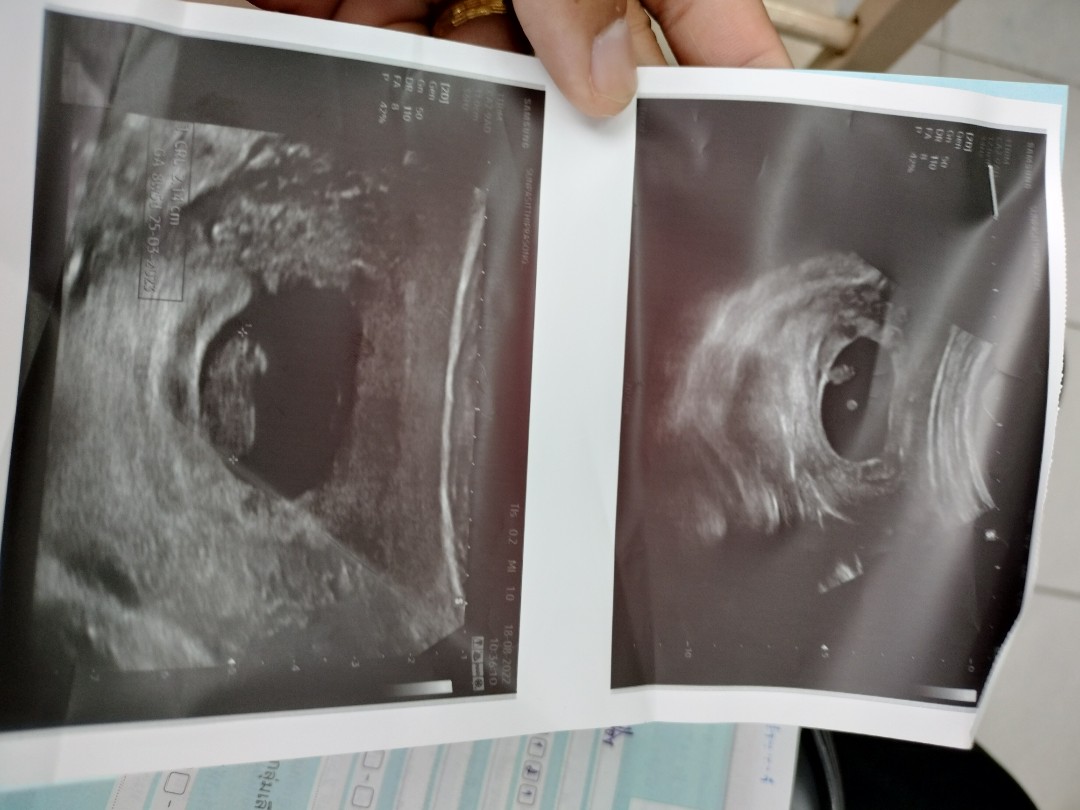

แต่ตอนนี้หนูได้ตั้งครรภ์อีกรอบเป็นรอบ2คือแอบกังวนจะท้องลมอีกรอบค่ะ มีแม่ๆๆบ้านไหนเคยเป็นแบบหนูไหมค่ะตอนนี้แอบกังวนมากๆๆค่ะ วันที่18นี้น่าจะครบ2เดือนกว่าจะไปหาคุณหมออีกรอบค่ะไปรอบแรกหมอซาวยังไม่เจอเด็กค่ะหมอบอกยังท้องอ่อนๆอยู่ขอกำลังใจหน่อยค่ะ😂✌️

ในที่สุดก็เจอน้องพร้อมเสียงหัวใจคะ❤️❤️

เจอน้องแล้วจ้าา💗